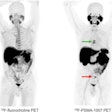

Prostate cancer study describes PET scoring system